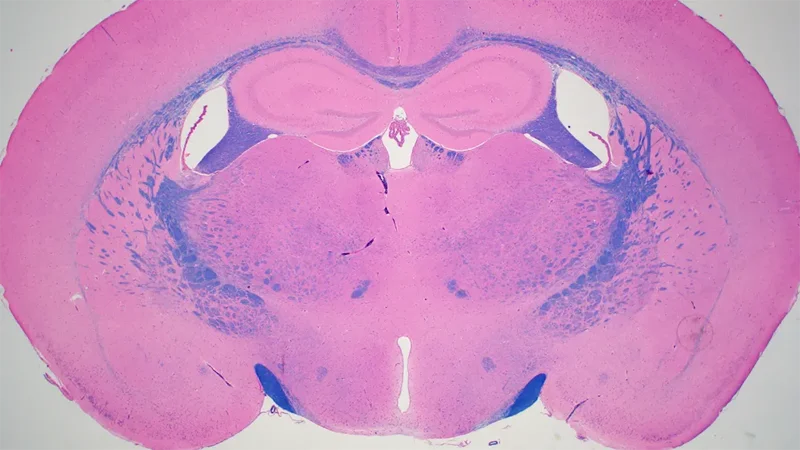

Histopathology Sciences (HPS) provides cutting-edge services enabling analysis of a wide range of anatomical, biochemical, protein, cell, and cell surface characteristics in tissue, blood, urine, and cerebrospinal fluid from various mouse models. The results are critical for numerous and varied phenotyping studies, monitoring disease progression, and determining response to drug treatments or effects of environmental factors. For example, investigators using mouse models of retinopathy rely on the work of HPS to identify lesions in the eye using both Histology and Electron Microscopy Services. The Histology and Clinical Chemistry Services partner with the JAX Diagnostic Program team and Clinical Pathologists to safeguard the health of JAX mouse colonies through the JAX colony monitoring program. The Histology and Electron Microscopy Services can also process fixed human tissue or cultured cell samples, patient-derived xenografts, and non-mammalian vertebrate samples. Our managers and experienced staff are available for consultation. Working together, they provide experimental design support and establish workflows to ensure that investigators can obtain the clearest results for their research.